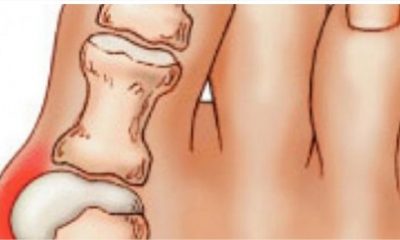

Деформираните коски или зглобови по рацете или стапалата се вистинско мачење, особено ако носите тесни чевли. Со цел да ги излекувате болките, подгответе го следниов едоставен рецепт....